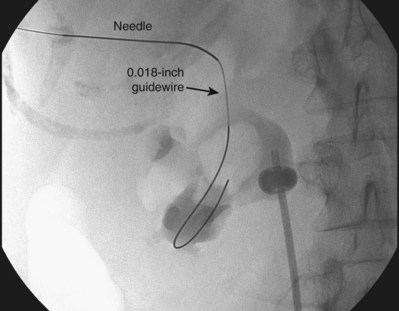

The general scheme of antegrade access is to place a needle through the skin into the upper urinary tract collecting system. Through the needle a guidewire is placed and then over the guidewire are placed catheters and other devices, eventually enlarging the tract until the desired lumen is reached for the purpose of the procedure. This is the Seldinger technique, described (for vascular access) by Sven-Ivar Seldinger (1953). The standard choices for the needle are a 21-gauge needle through which is passed a 0.018-inch guidewire or an 18-gauge needle through which is passed a standard 0.035-inch guidewire. Both needles have a blunt sheath and a sharp obturator (Fig. 47–15). The 21-gauge needle has the advantage of causing relatively minor injury as it is passed through tissue. Multiple passes can generally be made with little risk of hemorrhage from the needle itself; the option to place and replace the needle multiple times is advantageous because getting the tip of the needle into the right spot in the kidney is the most difficult aspect of percutaneous access into the upper urinary tract collecting system. The 18-gauge needle is more traumatic, and multiple passes should be avoided. The advantage of the 18-gauge needle is that it is stiffer. In a number of circumstances the 21-gauge needle does not maintain trajectory adequately (e.g., scarred kidney, obese patient) and the 18-gauge needle is more effective. In addition, the 0.018-inch guidewire that passes through the 21-gauge needle (Fig. 47–16) must be exchanged for a standard 0.035-inch guidewire for subsequent tract dilation or catheter placement. This requires an extra step, which adds to the complexity of the procedure and increases the risk of loss of access. Balancing the reduced efficacy of the 21-gauge needle and its increased potential for loss of access, versus the increased risk of trauma with the 18-gauge needle, it is recommend that the 21-gauge needle be used when the operator is less experienced or if minimizing trauma is paramount. The 18-gauge needle should be used when an experienced operator is confident that the tip of the needle can be placed within the desired calyx with just a few attempts.

Figure 47–16 0.018-inch guidewire passed through percutaneous needle. This wire is exchanged for a 0.035-inch guidewire for subsequent manipulation.